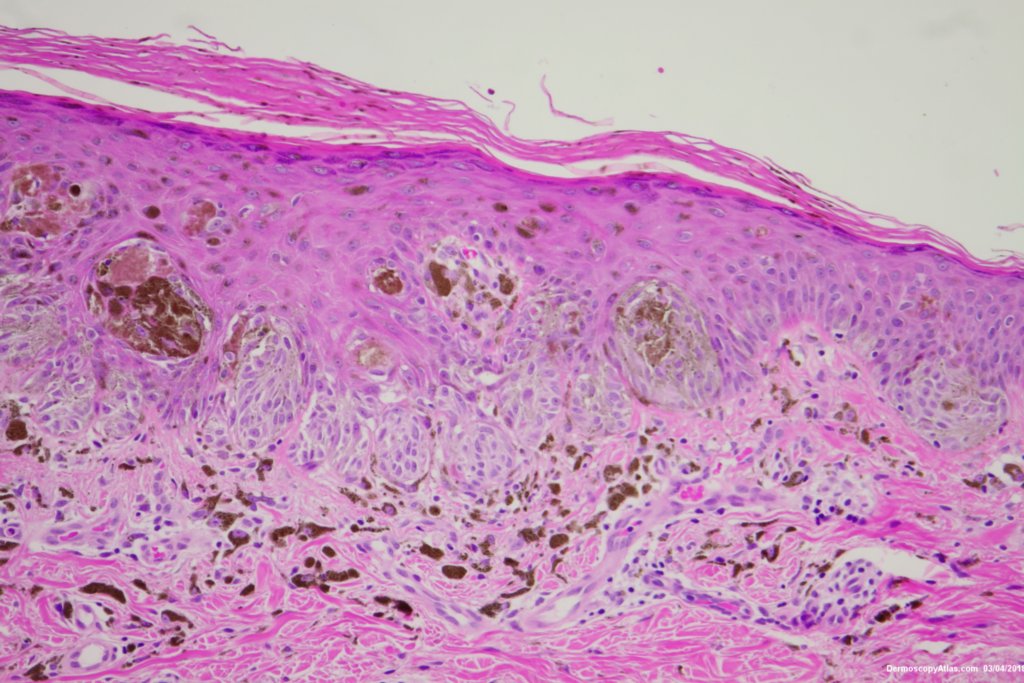

Diagnosis: Reed nevus

Sudden onset of a new pigmented lesion on the shoulder. Dermatoscopy shows an actively proliferating lesion with peripheral pseudopods that involve most of the circumference. Clinically this was either a Reed nevus or a Spitzoid melanoma. The histology favours a Reed nevus.